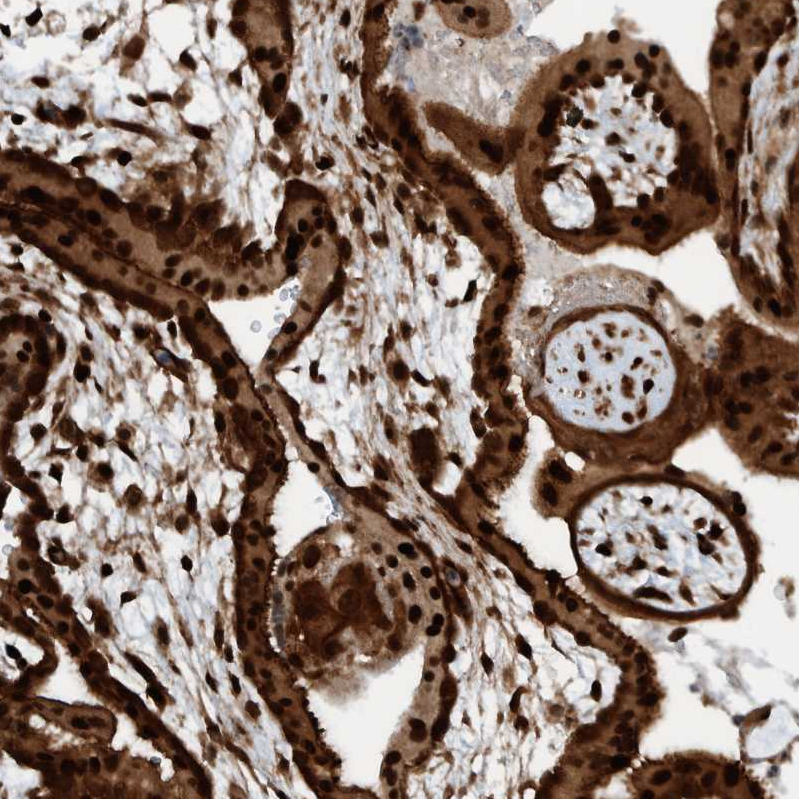

Immunohistochemical staining of human placenta shows strong nuclear/cytoplasmic nuclear positivity in trophoblastic cells.